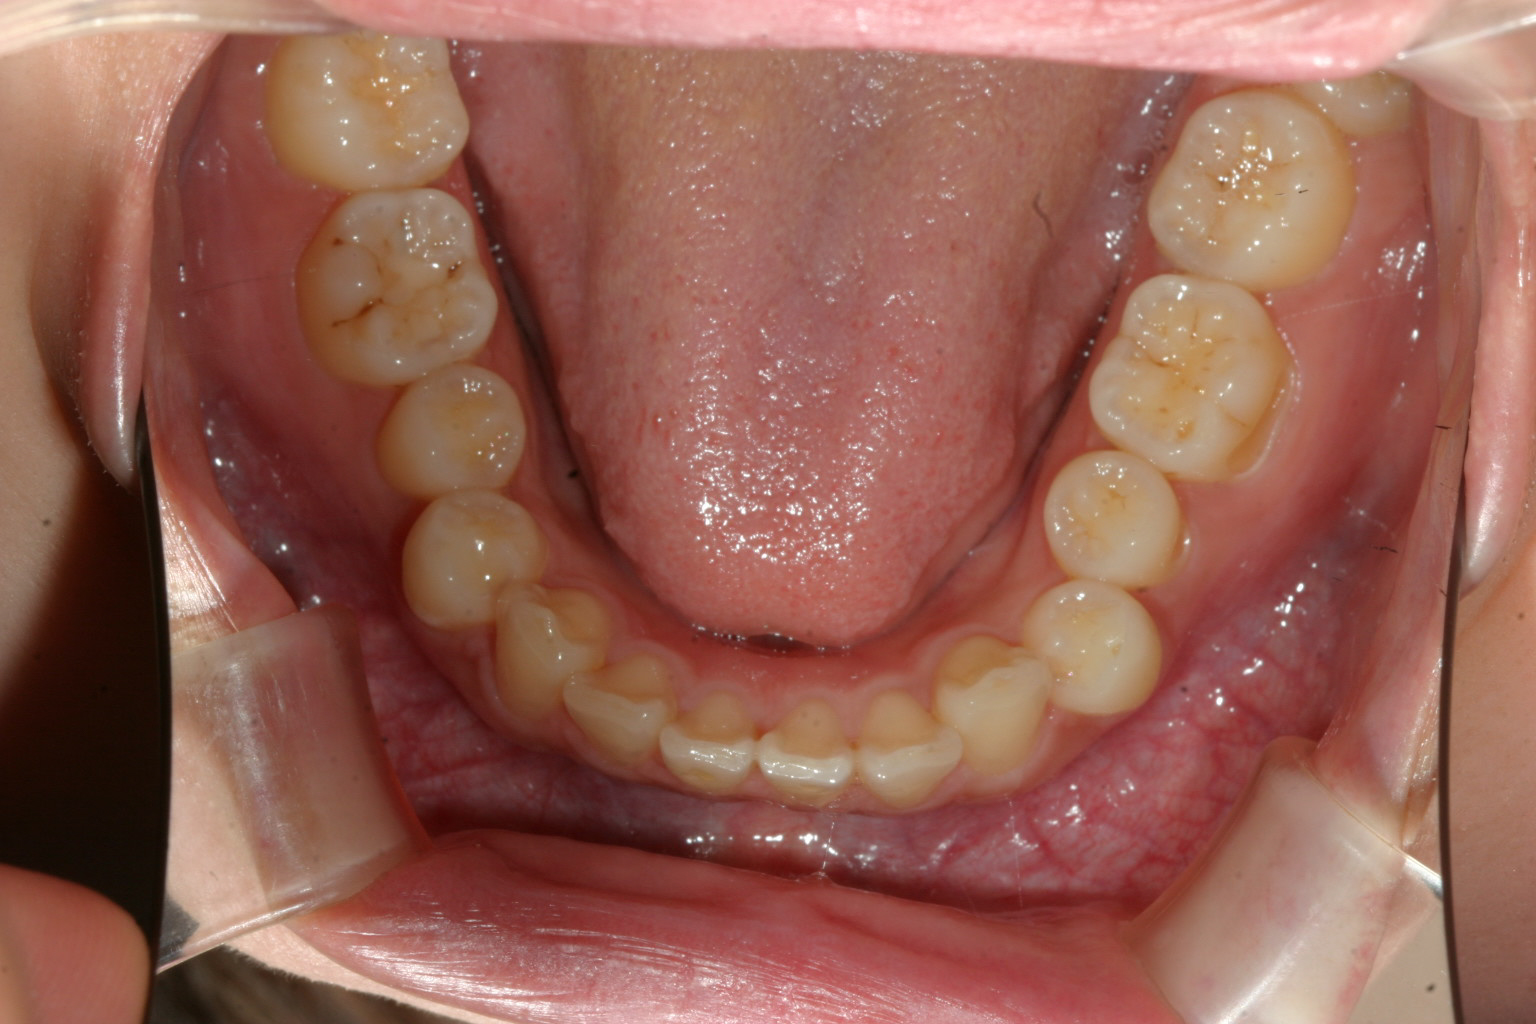

下顎は綺麗な歯並びですね~

下顎は元からそんなに乱れてませんから治療前とさほど変わりません。